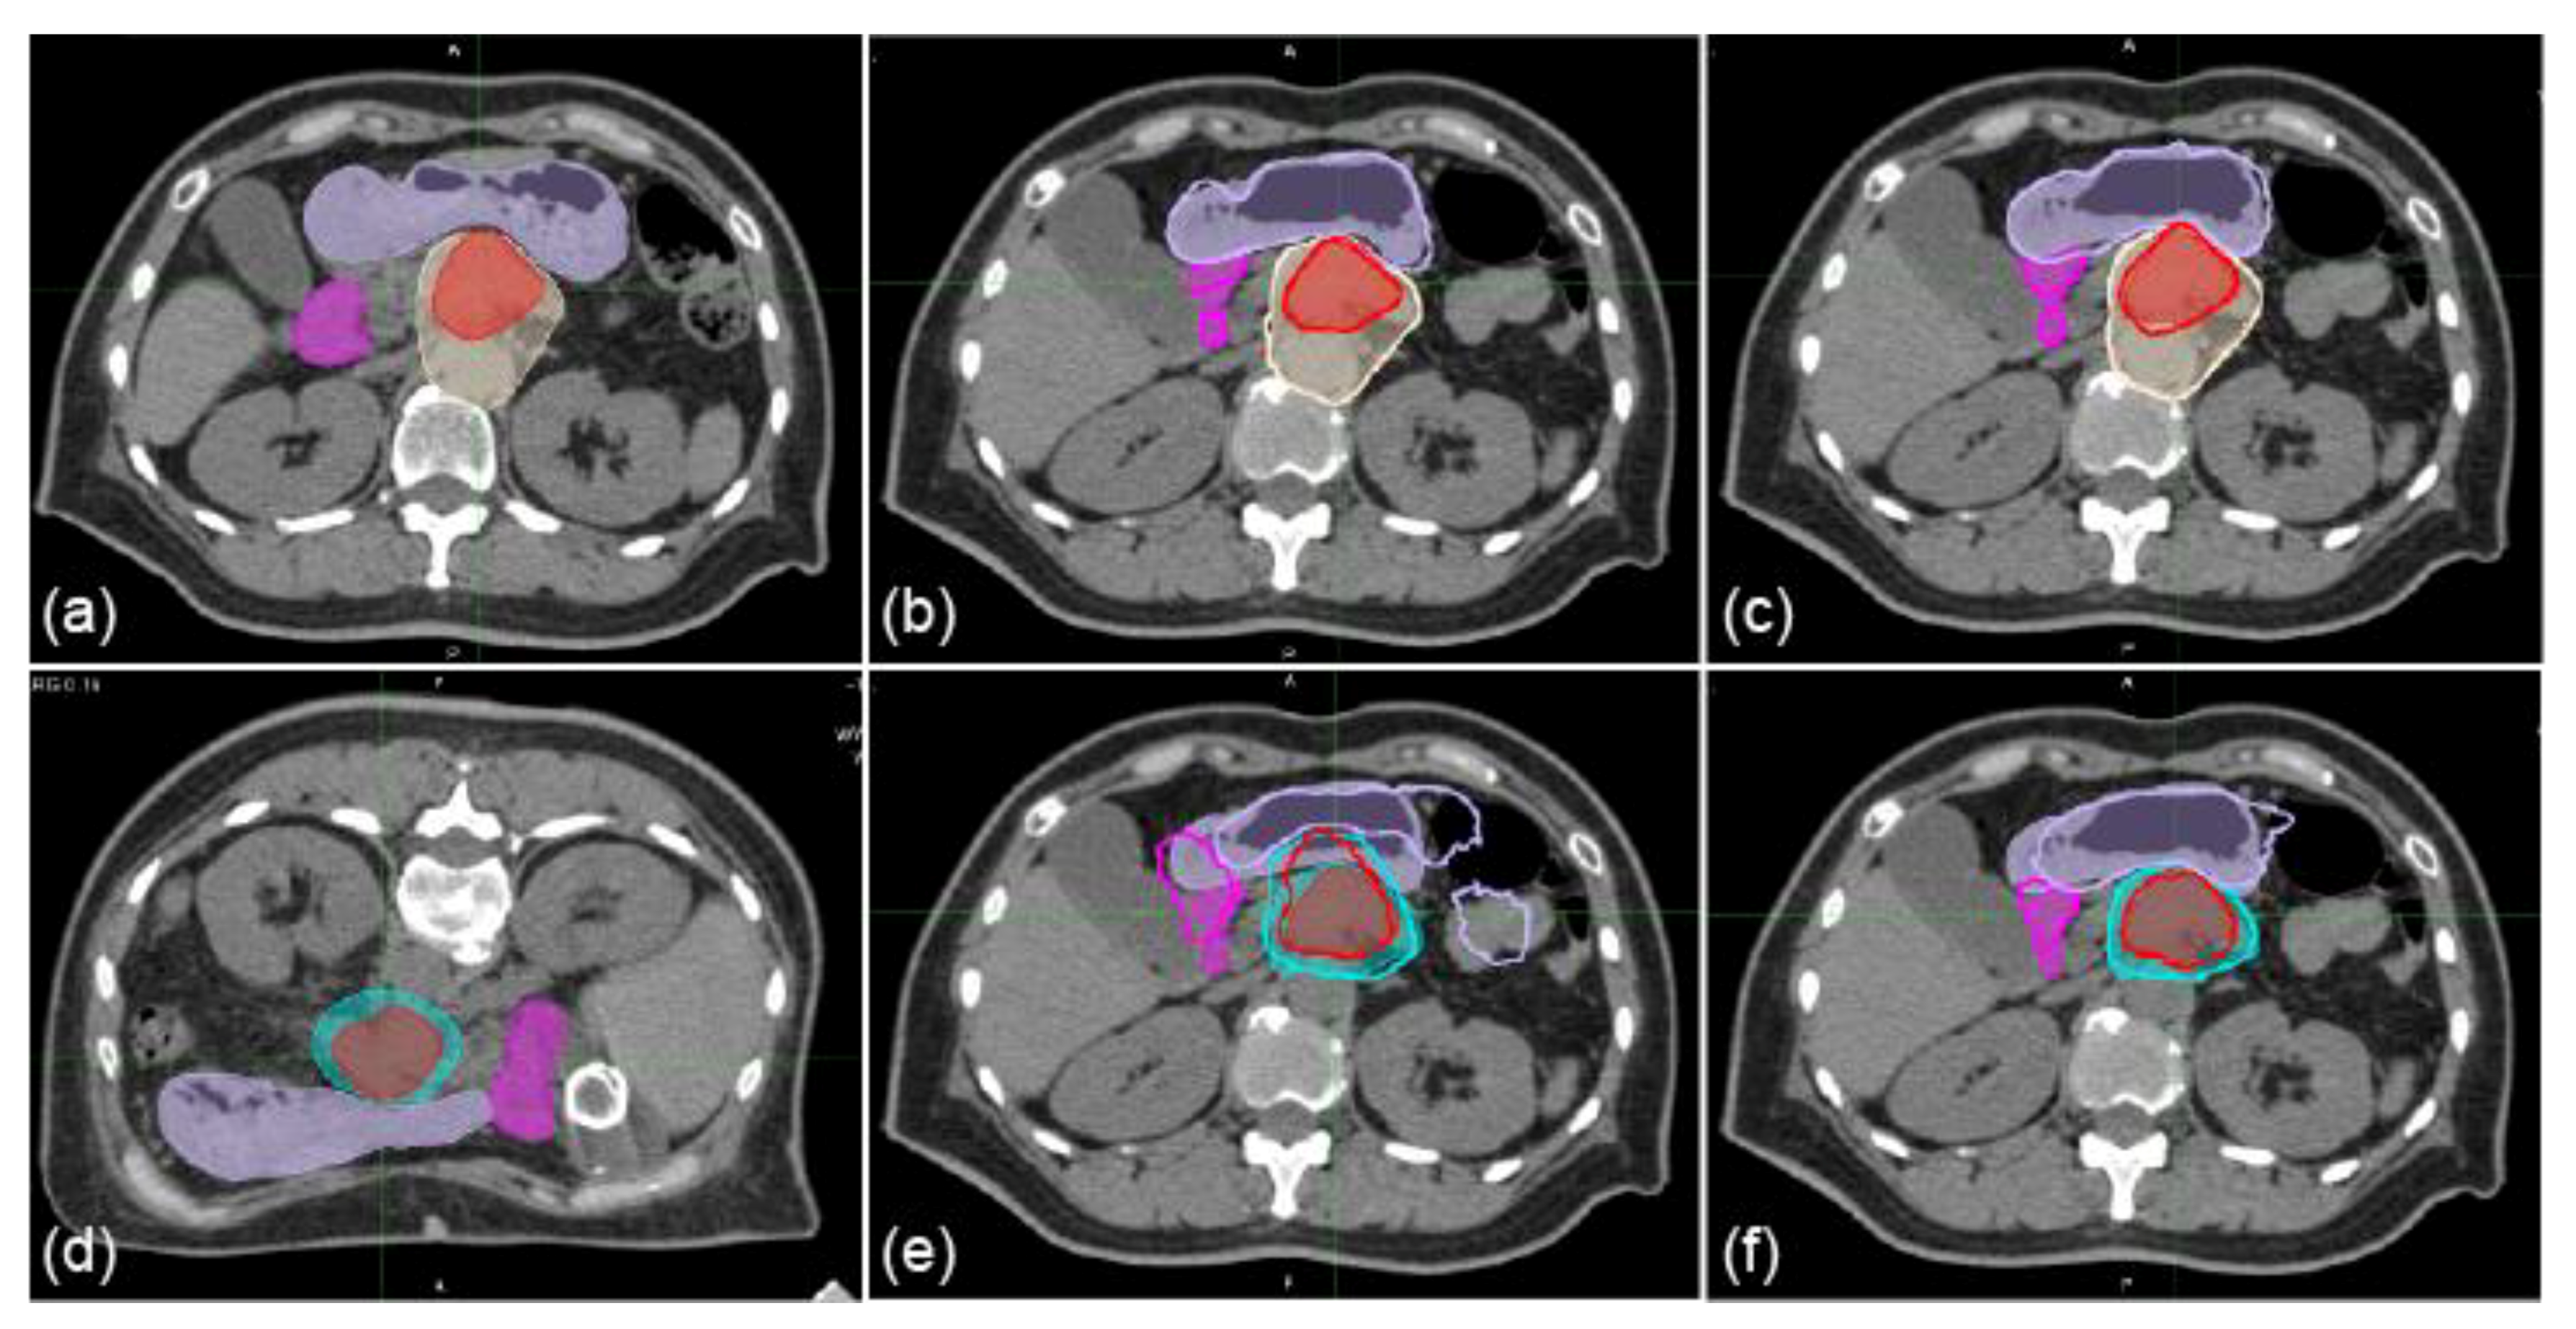

Sample CT images with transferred contours and dose distributions of supine and prone positions are shown in Figure 1 and Figure 2, respectively. The dice similarity coefficient (DSC) and mean displacement to agreement (MDA) for each contour for all patterns are shown in Figure 3. In all cases, the means ± standard deviation of the DSCs of all contours (n = 72) were 0.72 ± 0.20, 0.81 ± 0.16, 0.86 ± 0.11, and 0.87 ± 0.08 with RIR, intensity-based DIR (iDIR), contour-based DIR (cDIR), and hybrid iDIR-cDIR (hDIR), respectively; the means ± standard deviation of the MDAs were 3.40 ± 3.30, 2.21 ± 2.48, 1.46 ± 1.49, and 1.46 ± 1.37, respectively. There were significant differences between RIR and the other registration methods for both the DSCs and MDAs (p < 0.001 for all combinations). Moreover, the DSCs and MDAs of cDIR and hDIR were significantly better than those of RIR and iDIR (for both DSCs and MDAs, p < 0.001 for cDIR vs. RIR, and hDIR vs. RIR). For registration from the first irradiation day (1st-IRCT) to the supine position CT images for treatment planning (SP-PlanCT) (SP-SP) cases, the MDAs were less than 2 mm in 45.8% of RIR cases, 83.3% of iDIR cases, 100% of cDIR cases, and 95.8% of hDIR cases. The corresponding values for registration from the 10th-IRCT to the prone position CT images for treatment planning (PR-PlanCT) (PR-PR) cases were 54.2%, 79.2%, 95.8%, and 91.7%, respectively, while for registration from the PR-PlanCT to the SP-PlanCT (SP-PR) cases they were 37.5%, 33.3%, 54.2%, and 54.2%. Differences in the dose-volume parameters for all patterns are shown in Table 1. In all cases, the median differences for (clinical target volume (CTV) V95 were 2.47%, 1.65%, 2.24%, and 1.50% for RIR, iDIR, cDIR, and hDIR, respectively; for gross tumor volume (GTV) V95 the corresponding values were 0.84%, 0.81%, 2.47%, and 1.59%; for stomach V50 they were 1.60%, 2.94%, 0.85%, and 7.56%; and for duodenum V50 they were 0.68%, 0.91%, 0.58%, and 0.68%. Graphs showing the correlations between MDA and DSC, and between MDA and dose-volume parameters, are shown in Figure 4. The correlation coefficients R between MDA and DSC were 0.92, 0.93, 0.91, and 0.84 for RIR, iDIR, cDIR, and hDIR, respectively; the corresponding values between MDA and target (CTV and GTV) V95 were 0.47, 0.65, 0.56, and 0.40; and between MDA and organs at risk (OAR) (stomach and duodenum) V50 they were 0.01, 0.29, 0.23, and 0.44.

The correlation coefficients R between MDA and DSC were high (0.84–0.93), as shown in Figure 4. Although DSC accuracy generally increases as the volumes increases, DSC can be used for evaluating DIR accuracy in pancreatic cancer patient images because it has a high correlation with MDA. In contrast, the correlation coefficients between MDA and V95 for the target were only mid-range (0.40 to 0.65), because differences in the target V95 might decrease when registration accuracy increases. The correlation coefficients between MDA and V50 for the OARs were low (0.01, 0.29, and 0.23 with RIR, iDIR, and cDIR, respectively). It is not necessarily the case that the differences in the OAR V50 decrease when registration accuracy increases.

Figure 4. Correlations between mean displacement to agreement (MDA) and DSC (ad), and MDA and absolute difference of V95 of CTV and GTV or V50 of stomach and duodenum (eh). Red markers show the results of SP-SP cases, blue markers PR-PR cases, and green markers SP-PR cases. Squares represent target (CTV and GTV) and organs at risk (OARs) (stomach and duodenum), filled circles represent target, and hollow circles OAR. (a,e) show RIR, (b,f) show iDIR, (c,g) show cDIR, and (d,h) show hDIR. The black line in (ad) indicates a regression curve fitted with an exponential function. The black and black-dotted lines in (eh) show regression lines fitted with a linear function for the target and OAR, respectively.